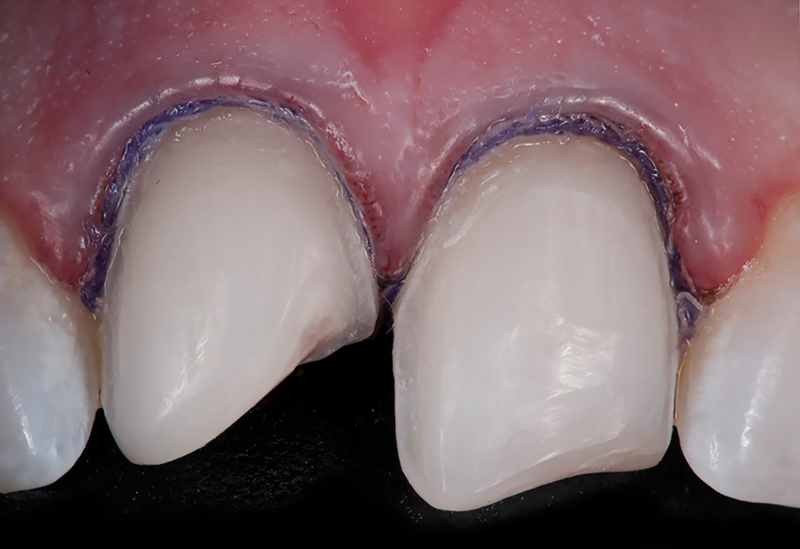

Fig 2. Preoperative (Fig 1), preparation (Fig 2), and final (Fig 3) postoperative images of a two-unit CL-I feldspathic veneer case.

Figure 2

Class I (CL-I) powder and liquid porcelains are created from materials primarily containing silicon dioxide and possess a glassy matrix and varying amounts of a crystalline phase within the glassy matrix (eg, Creation Porcelain, Jensen Dental, jensendental.com; Ceramco 3, Dentsply Sirona, dentsplysirona.com; EX-3, Kuraray Noritake Dental, Inc, kuraraynoritake.com). The CL-1 group includes feldspathic porcelains, referred to as such because they were originally—and some continue to be—made from naturally occurring feldspars (ie, aluminosilicates composed of assorted quantities of potassium, sodium, barium, or calcium).9,17 Several feldspathic material options are available on the market today (eg, VITA VM 13, VITA Zahnfabrik, vita-zahnfabrik.com; Vintage Halo, Shofu, shofu.com) (Figure 1 through Figure 3).

CL-I materials are fabricated by hand (Figure 4); they are the most conservative and generally the most translucent ceramic materials, but they are also the weakest.9,10,18 The material's high translucency and esthetics create the illusion of natural teeth.9 Powder/liquid porcelain materials are ideal for cases in which significant enamel remains and/or there is healthy tooth structure on the teeth (ie, 50% or more remaining enamel on the tooth, 50% or more of the bonded substrate is enamel, and 70% or more of the margin is in the enamel). Feldspathic porcelain restorations that are bonded to primarily enamel substrates have proven to be highly successful long term.19

Powder/liquid porcelains demonstrate high esthetics and workability, and because they can be layered very thinly and placed directly on the enamel, they are considered the most conservative of the metal-free ceramic classes.10 CL-I porcelains require a thickness of 0.2 mm to 0.3 mm for each shade change.20,21